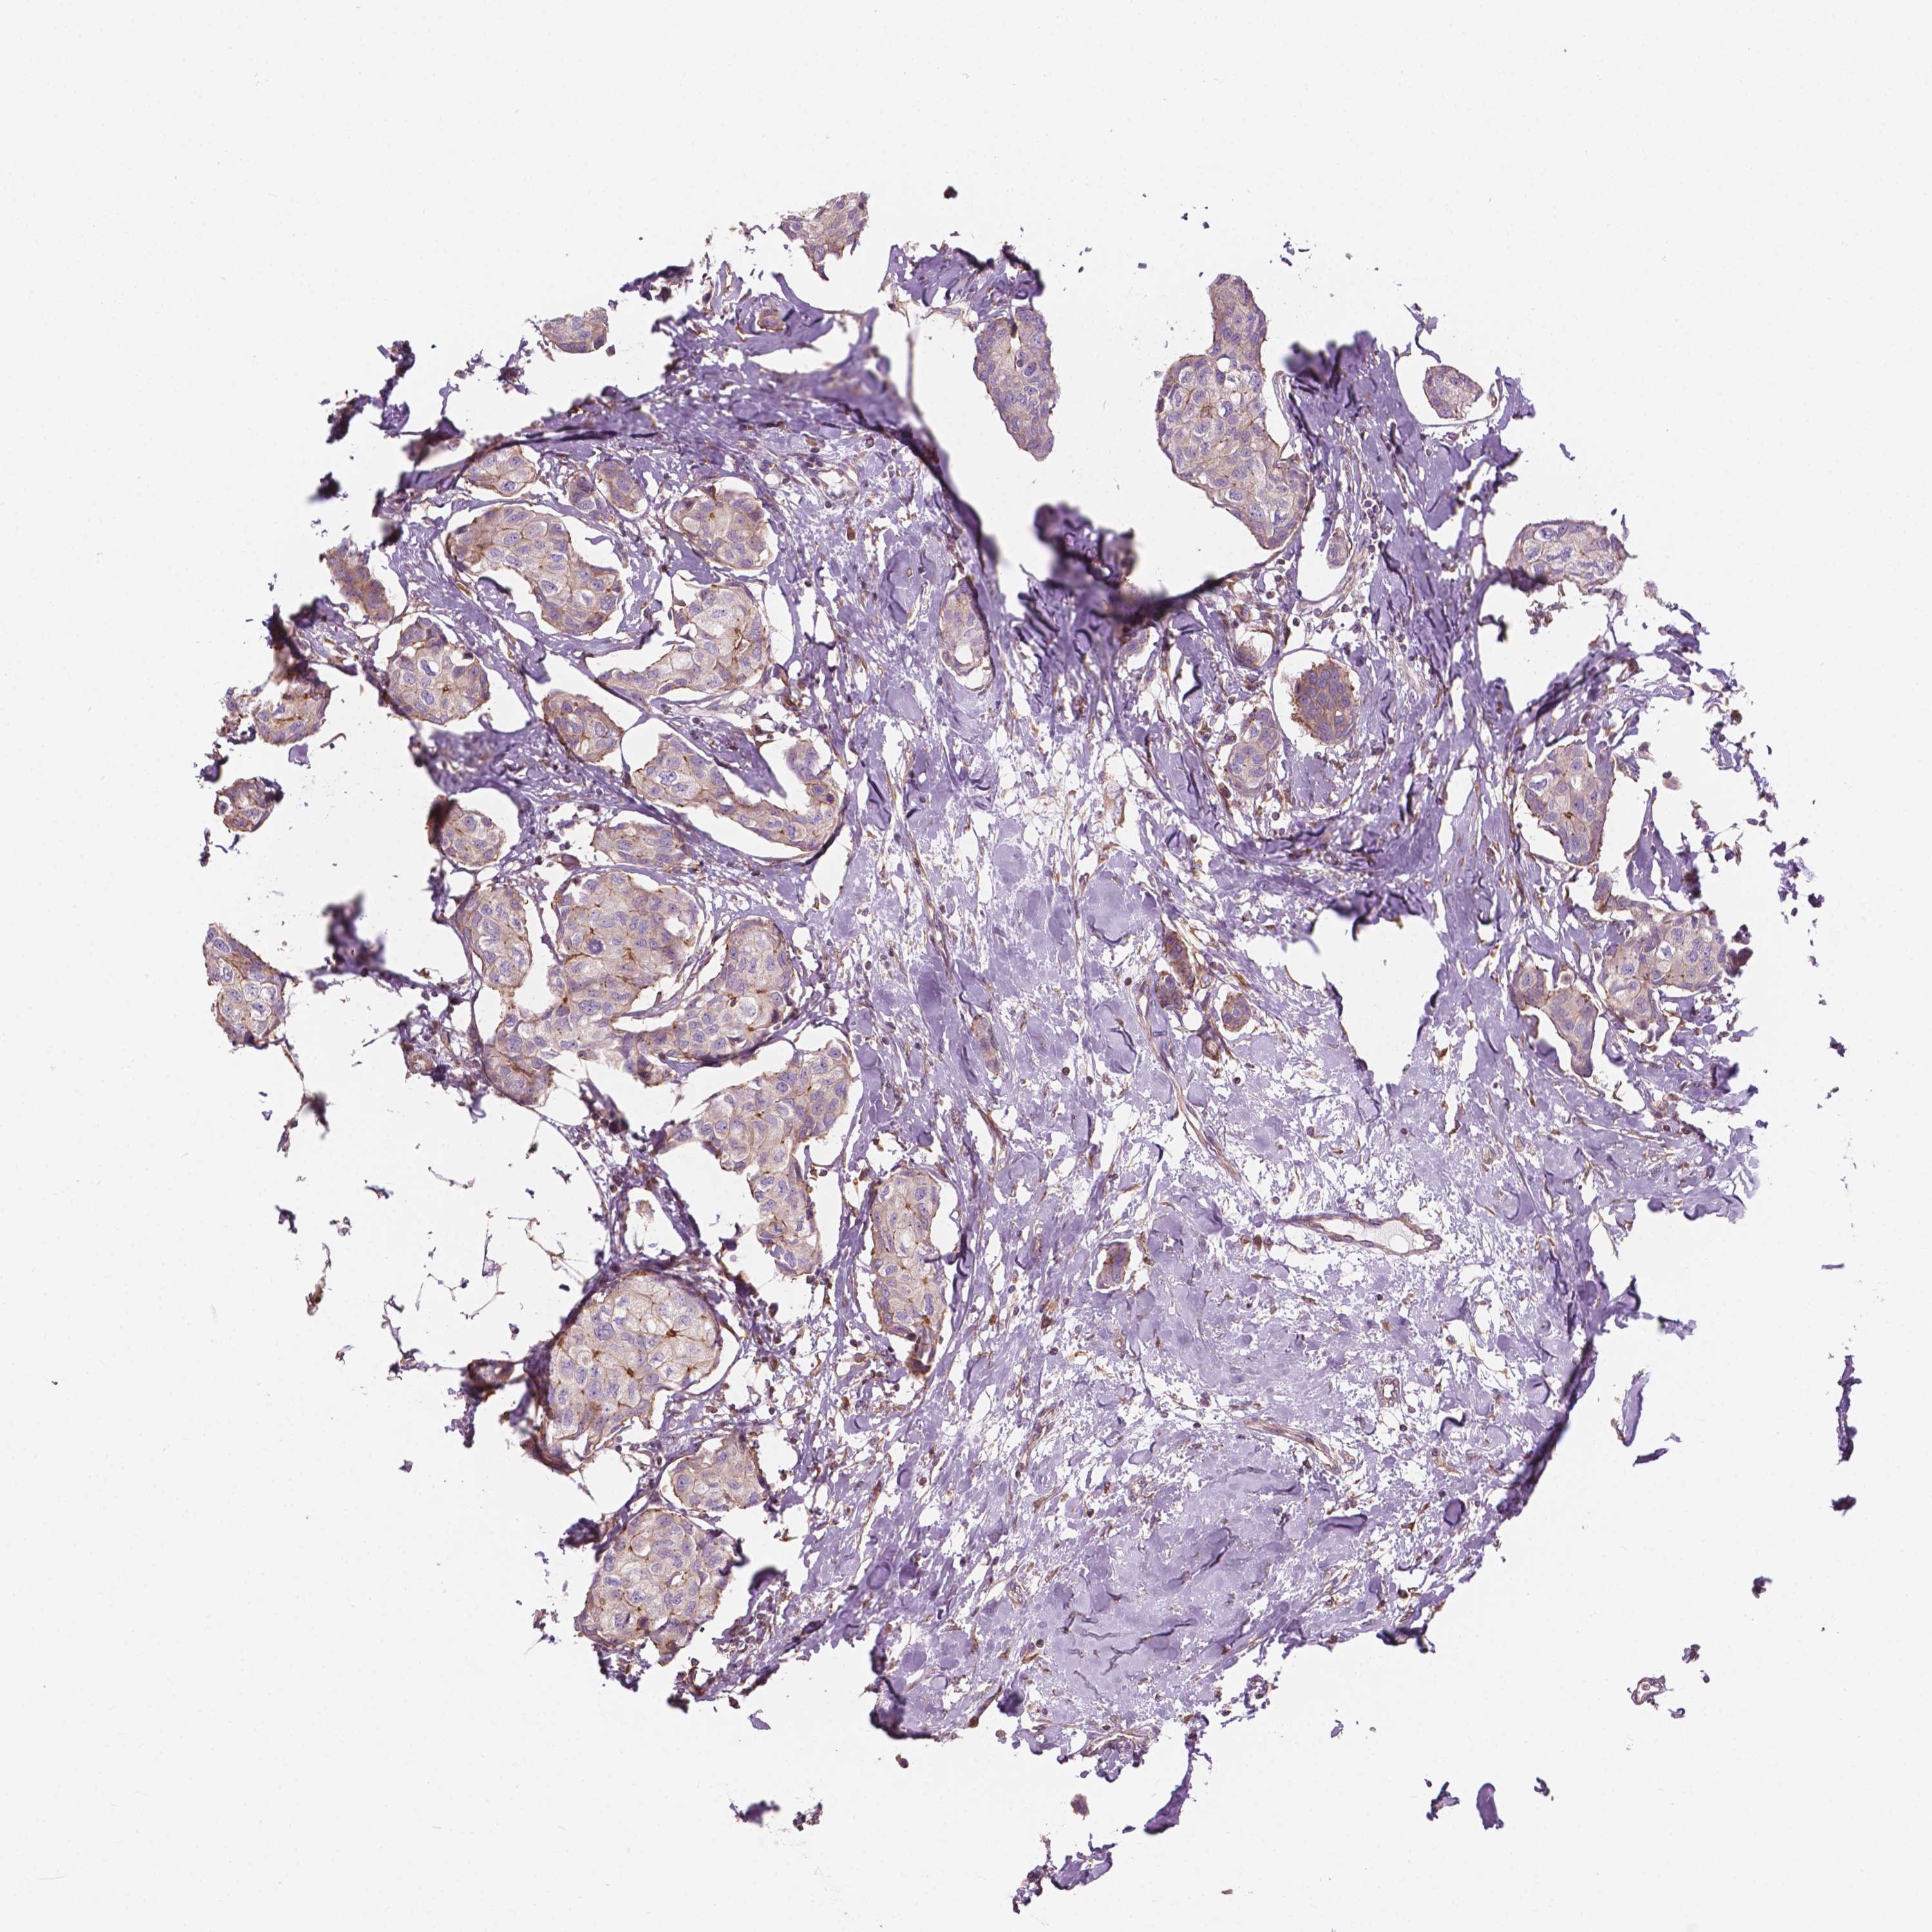

CANCER BREAST CANCER Show tissue menu

BRCA TCGA BRCA VALIDATION PROTEIN EXPRESSION